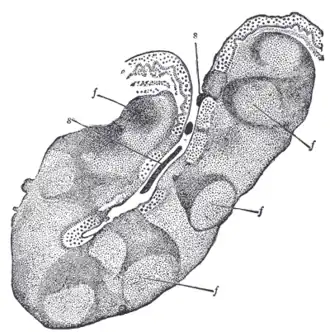

| A tonsillolith lodged in the tonsillar crypt | |

Tonsil stones, also known as tonsilloliths, are mineralizations of debris within the crevices of the tonsils.[1][3] When not mineralized, the presence of debris is known as chronic caseous tonsillitis (CCT).[1] Symptoms may include bad breath,[1] foreign body sensation, sore throat, pain or discomfort with swallowing, and cough.[4] Generally there is no pain, though there may be the feeling of something present.[1] The presence of tonsil stones may be otherwise undetectable; however, some people have reported seeing white material in the rear of their throat.

Risk factors may include recurrent throat infections.[2] Tonsil stones contain a biofilm composed of a number of different bacteria, and calcium salts, either alone or in combination with other mineral salts.[5][1] While they most commonly occur in the palatine tonsils, they may also occur in the adenoids, lingual tonsils and tubal tonsil.[3][6][7] Tonsil stones have been recorded weighing from 0.3 g to 42 g,[3] and they are typically small in size. However, there are occasional reports of large tonsilloliths. They are often discovered during medical imaging for other reasons and more recently, due to the impact and influence of social media platforms such as TikTok, medical professionals have experienced an increase in patient concern and tonsillolith evaluations.[8][9]

The mechanism by which these calculi form is subject to debate,[3] though they appear to result from the accumulation of material retained within the crypts, along with the growth of bacteria and fungi—sometimes in association with persistent chronic purulent tonsillitis.

Tonsilloliths or tonsil stones are calcifications that form in the crypts of the palatal tonsils. They are also known to form in the throat and on the roof of the mouth. Tonsils are filled with crevices where bacteria and other materials, including dead cells and mucus, can become trapped. When this occurs, the debris can become concentrated in white formations that occur in the pockets.[12] Researchers found aerobic bacteria present on the surface of tonsilloliths and anaerobic bacteria at the core of tonsilloliths. They have the potential to cause oral halitosis as they contain volatile sulfur compounds and sulfur derived gases, foul smelling compounds produced during bacterial metabolism.[16] Tonsilloliths are formed when this trapped debris accumulates and are expressed from the tonsil. They are generally soft, sometimes rubbery. This tends to occur most often in people who suffer from chronic inflammation in their tonsils or repeated bouts of tonsillitis.[12] They are often associated with post-nasal drip.

Enlarged tonsil stones

Much rarer than the typical tonsil stones are giant tonsilloliths. Giant tonsilloliths may often be mistaken for other oral maladies, including peritonsillar abscess, and tumors of the tonsil.[17] On average, tonsil stones should appear within a similar range of the image shown here; however, individuals with extenuating cases have been reported. In these instances, extensive care such as extraction by a licensed medical professional may be needed.